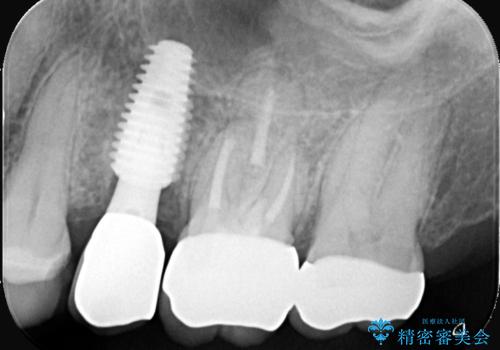

- 左上7番の銀歯の下に虫歯が発見されたケースです。患者様は機能性と審美性の両方を考慮し、オールセラミッククラウン(スタンダード)での修復を選択されました。オールセラミッククラウンは、天然歯に近い透明感を持ち、金属を使用しないため金属アレルギーのリスクも軽減されます。治療後は、違和感なく快適に噛めるようになり、自然な仕上がりに患者様も大変満足されました。

虫歯を取り除くと、歯の構造が弱くなり、破折のリスクが高まるため、修復には強度と耐久性のあるオールセラミッククラウン(スタンダード)を選択しました。